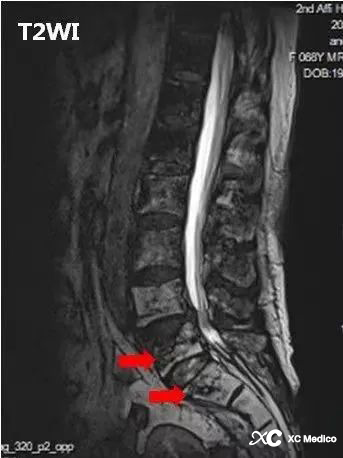

Гулентный дискрит позвоночника (PS) обычно вызван гематогенно диссеминированной инфекцией, причем Staphylococcus aureus является наиболее распространенным патогеном, чаще всего включающего поясничный позвоночник, а рентгеновские лучи отсутствуют специфичность и чувствительность на ранних стадиях заболевания. Увеличенная МРТ является методом выбора для ранней диагностики позвоночника; МРТ демонстрирует отек костного мозга и усиление тел позвонков, межпозвоночные диски, эпидуральное пространство и/или окружающие мягкие ткани с образованием или без абсцесса, расположенных главным образом рядом с конечными пластинами позвонка.

Примечание: (а) рентгенограмма с боковым поясничным позвоночником, показывающая потерю высоты диска L4 -L3 и разрушение верхней конечной пластины L4 (стрелка).

(б) легкий задний скольжение на L3. Разрушение диска L3 - L4 с эрозивными изменениями в соседних конечных пластинах (стрелки).

(C) Магнитно -резонансное изображение (MR), показывающее эрозивные изменения конечных пластин позвонка и аномальный сигнал соседнего костого мозга позвоночного (стрелка). Перевертебральные мягкие ткани заметно являются эдематозными и имеют воспалительные изменения.

(D) Сагиттальный T1 после внутривенного введения контрастного инъекции показывает усиленный сигнал в костном мозге (звездочка), усиленный сигнал в эпидуральном пространстве и мягких тканях с довертебральной. Обратите внимание на отступление центрального канала (стрелка).